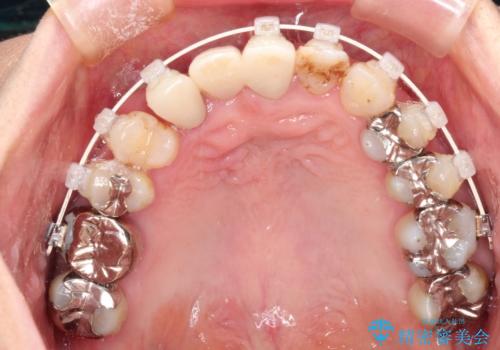

矯正を併用した前歯のセラミックブリッジ治療

- 上顎前歯をきれいにしたいとのことで来院されました。

レントゲンを撮影すると保存が難しい歯がありました。

またがたつきの度合いから歯を1本抜歯して矯正治療を行いセラミックブリッジを装着することで、審美的・機能的改善を行う計画としました。

治療の順序は

①保存不可の歯の抜歯・根管治療

②矯正治療

③セラミックの装着

という流れで行いました。